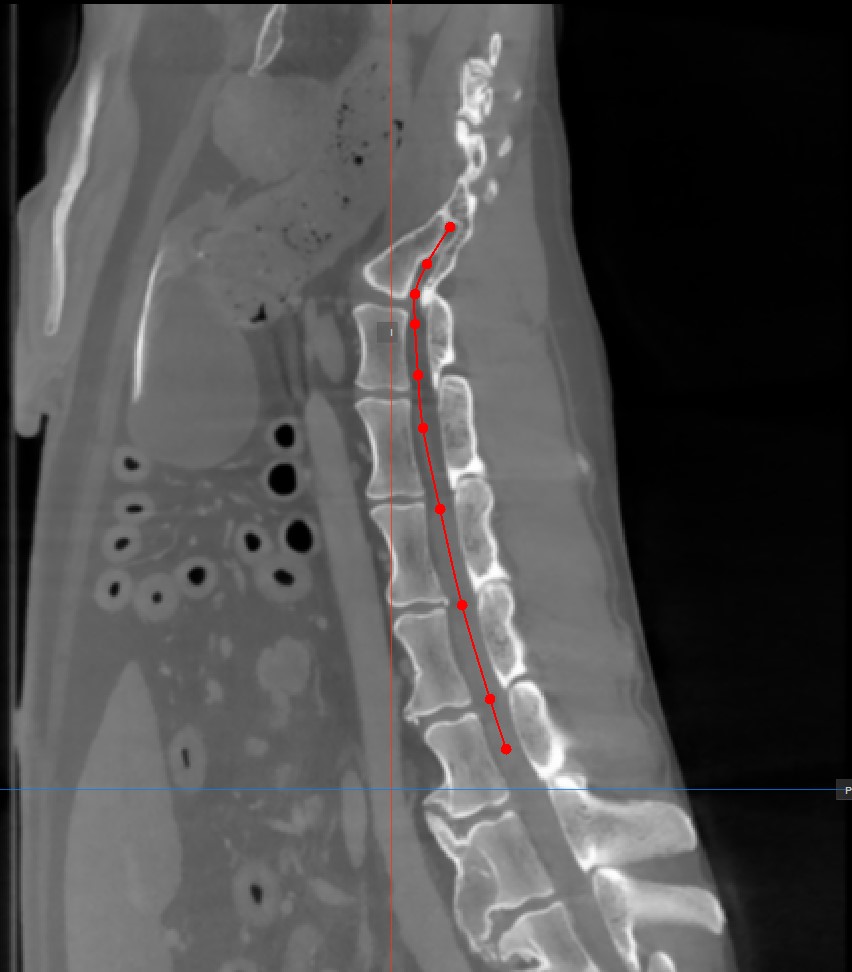

Add Curved Path Points¶

The Curved MPR requires a user-drawn path in order to generate the cross-sectional images. Select the Add CMPR Point tool located at the bottom section of the CMPR view to draw the required path.

The points generating the path have to be placed on one of the three available standard MPR viewports on the right side of the window. Choose the most appropriate plane for the requirements.

At least two points have to be placed on the images in order to generate the path. The CMPR view will be more detailed when more points are used to draw the path.

To complete the path, toggle the

Add CMPR Pointtool again, or double-click with the mouse on the image after placing the last point of the path. The path will be marked in green once it’s finalized.